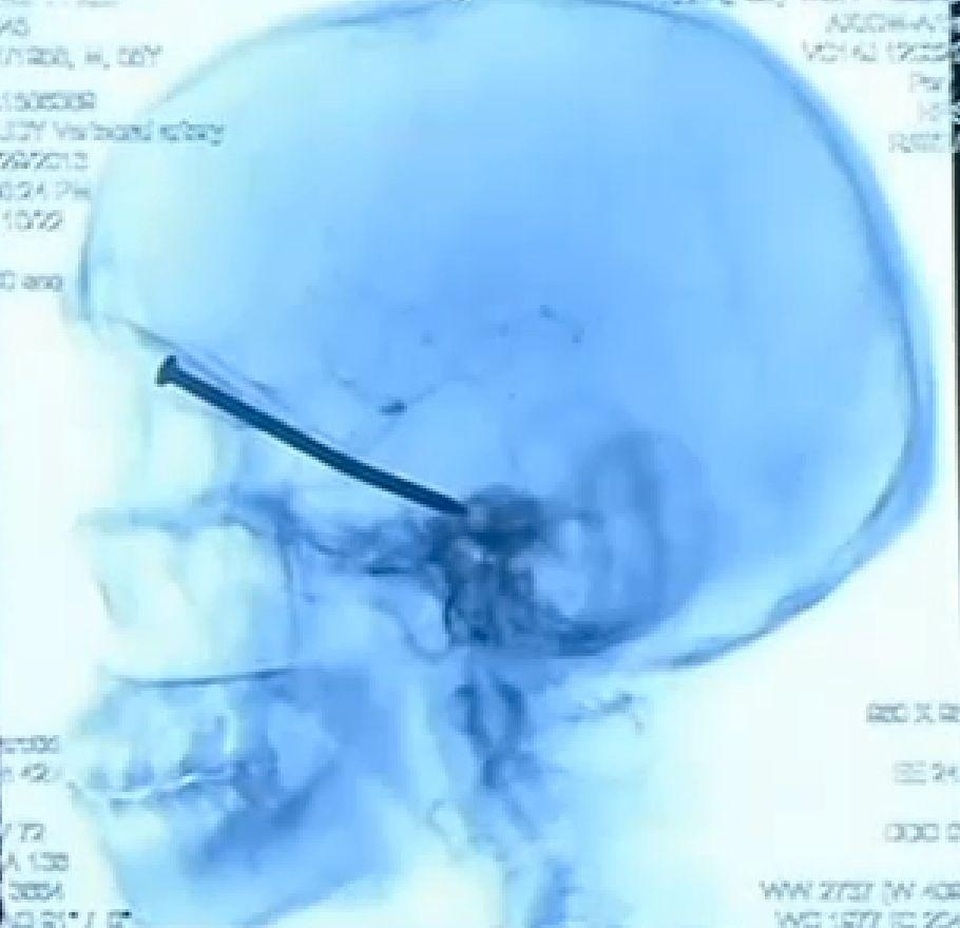

Ngày 31/1/2019, bức ảnh X-quang cho thấy con dao nằm sâu trong cằm của một thiếu niên Trung Quốc. Ren Hanzhi, 13 tuổi, đã bị trượt và ngã trong khi gọt táo và bị mũi dao đâm thẳng vào mặt. Thật kỳ diệu là lưỡi dao đã không chạm vào sọ não của cậu bé. Các bác sĩ đã rút dao thành công và hy vọng cậu bé sẽ hồi phục hoàn toàn.